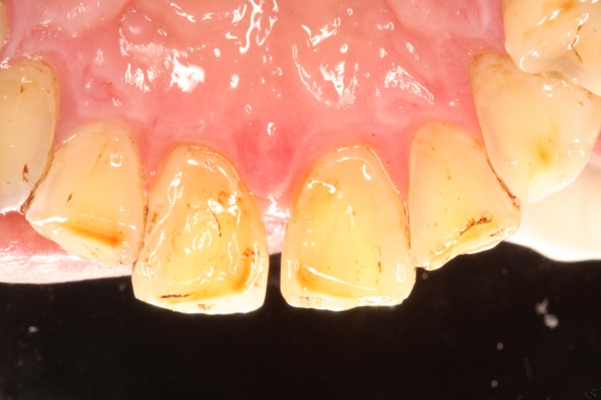

牙周炎圖片

牙周袋 (7)